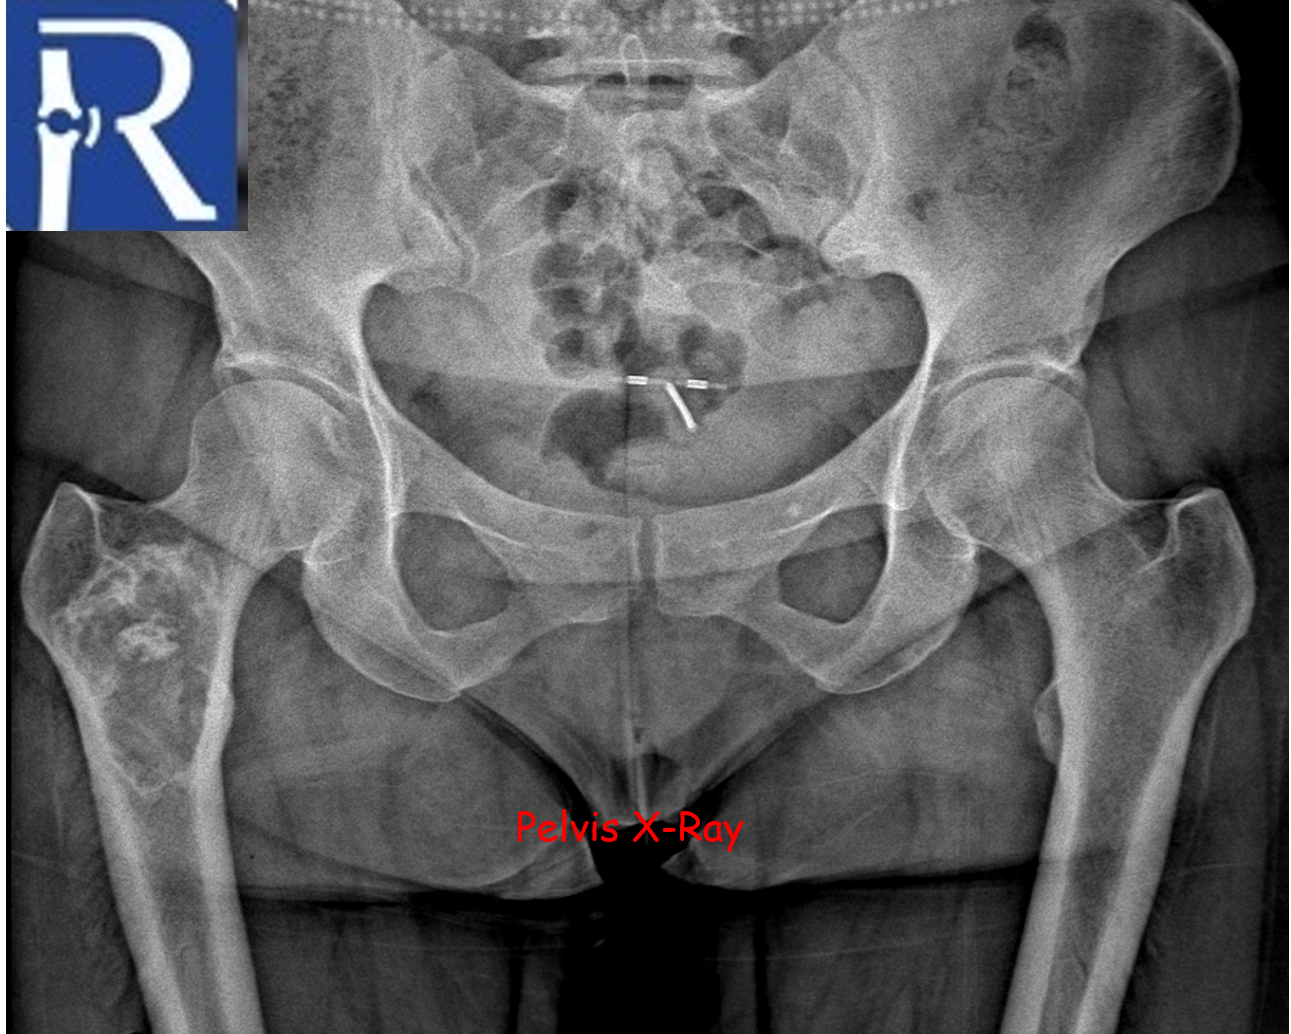

Liposclerosing Myxofibrous Tumor; Typical Location, Classical Radiologic Features

Clinical Findings: Incidental finding in a 42-year-old after trauma. Typical location, classic radiologic features

Imaging Findings:

A geographic lytic lesion of Type I A pattern (white arrows) is observed on the right femur intertrochanteric-subtrochanteric area on the pelvic radiograph. The lesion is well-circumscribed and has a narrow transition zone. The internal content contains calcification (indicated by the blue arrow). Periosteal reaction is not visualised. The lesion demonstrates sclerotic areas corresponding to internal calcified foci. The lesion is compatible with liposclerosing myxofibrous tumors. In CT, the lesion matrix structures are more clearly visible, and the cortex appears intact. Calcification areas in the internal structure are more clearly observed. In MRI, the lesion appears as a low signal on the T1-weighted (T1W) sequence and as a high signal on the short tau inversion recovery (STIR) sequence, representing the myxoid content. Additionally, the calcification areas within the lesion exhibit low signals in both sequences.